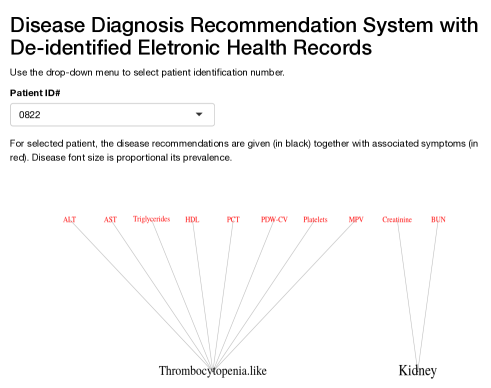

Latent disease 3 can be characterized as thrombocytopenia-like disease which causes low count of platelets, decreased plateletcrit (PCT) and coefficient of variation of platelet distribution (PDW-CV), and increased mean platelet volume (MPV). Patients with low platelets may not be able to stop bleeding after injury. In more serious cases, patients may bleed internally which is a life-threatening condition.

6.3 A Web application for disease diagnosis

A good user interface is critical to facilitate the implementation of the proposed approach in the decision process of healthcare providers, and for broad application. Using the R package shiny (Chang et al. , , 2015), we have created an interactive web application (available at https://nystat3.shinyapps.io/Rshiny/). The application displays disease diagnosis recommendations for de-identified patients selected by the user. We show the application for two patients in Figure 6.